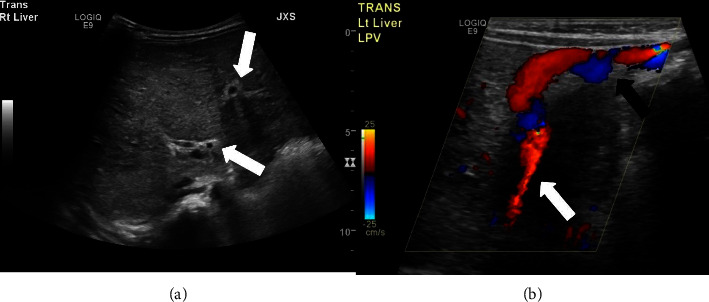

Congenital hepatic fibrosis is a rare, autosomal recessive, fibro-polycystic disease resulting from ductal plate malformation, leading to proliferation and fibrosis of bile ducts. Progressive hepatic fibrosis leads to portal hypertension and varices which can present with life threatening gastrointestinal hemorrhage. We report a case of congenital hepatic fibrosis in a 2-year-old child who presented with 8 days of fever without any significant medical history or physical examination findings.